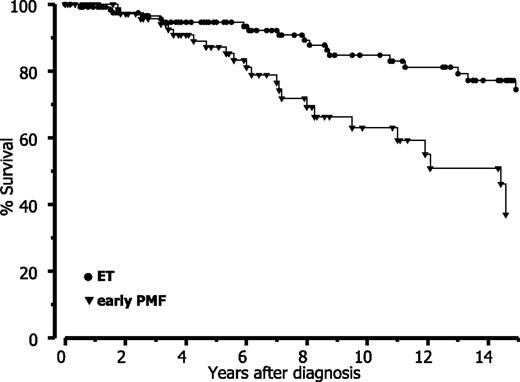

Finally, when strictly applying the WHO criteria, our data revealed that prognosis is significantly reduced in early PMF with thrombocythemia compared with (true) ET. Based on a long-term follow-up (Table 6), estimated mean survival data are comparable with the Cologne cohort for both entities if the differences in follow-up and amount of censored patients are considered. Accordingly, this analysis shows a significant (P < .0001) difference of approximately 7 years between ET and early PMF and consequently also a different relative survival (Figure 6).

Relative survival in ET versus early-prefibrotic PMF according to WHO diagnosis in the Vienna cohort.

Relative survival in ET versus early-prefibrotic PMF according to WHO diagnosis in the Vienna cohort.

An accurate distinction between ET and early PMF with excess in platelets (false ET) is not a matter of semantics but may exert an influence on decisions for therapeutic strategies and, most important, complications and outcome. Concerning prognostic differences under standard therapy, former studies from Cologne14,15 demonstrated a significant worsening of survival in early PMF contrasting ET diagnosed according to the WHO criteria.1,16 This result is confirmed and extended by this study, and it cannot be overemphasized that in this regard comparative data from the Vienna cohort of patients are matching with the large historical series of Cologne characterized by a very long follow-up. All this provides persuasive evidence that strict adherence to the WHO-defined ET diagnosis, survival appears to be significantly more favorable than previously reported.32,41-43 In this regard, it may be speculated that these striking features have been partially and involuntarily unveiled in an indirect fashion by the already discussed paper on “reticulin” (ie, correct reticulin and/or collagen) accumulation in so-called ET regarding laboratory data as well as complications but especially prognostic significance.5 After statistical analysis, patients presenting with moderate to overt BM fibrosis (fiber grades 3 to 4)36 at onset. This finding is comparable with survival data describing prognosis in early-prefibrotic versus fibro-osteosclerotic stages of PMF.14,15,19,30